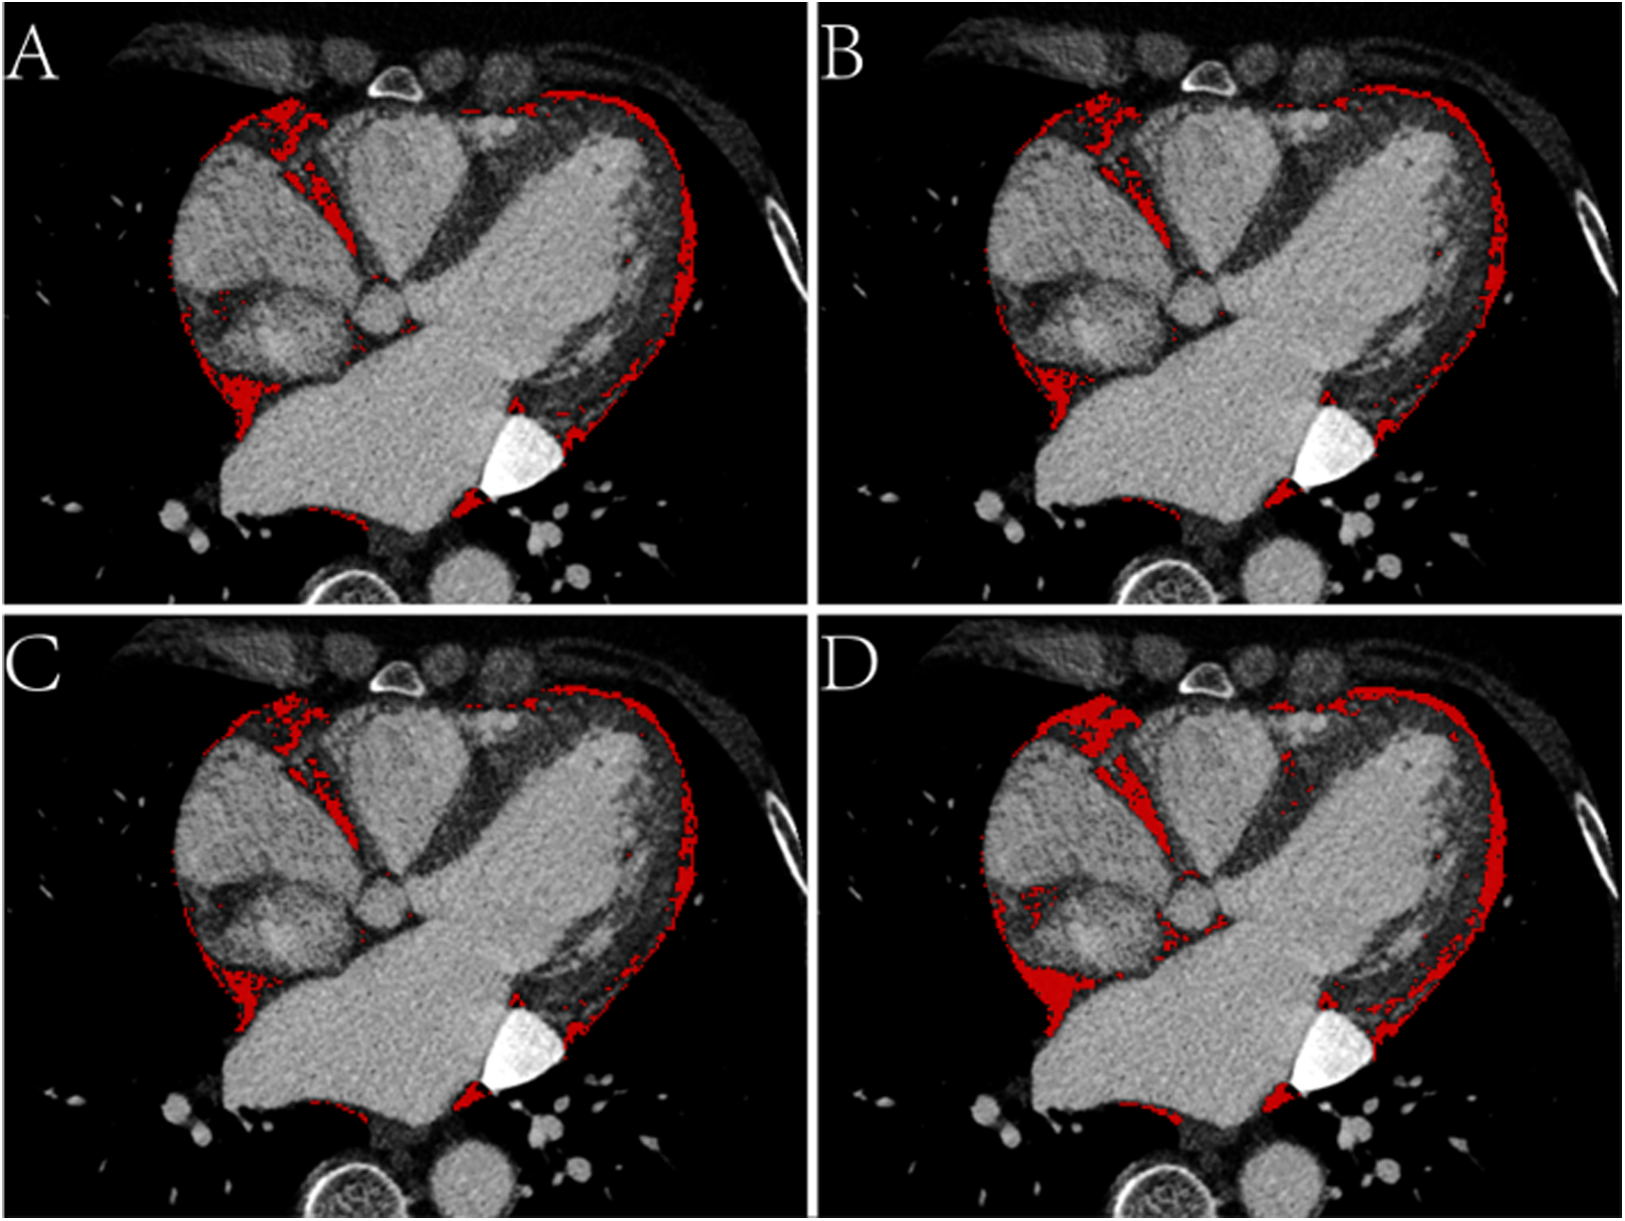

EAT volume and density were calculated using postprocessing software on a SyngoVia workstation (Cardiac Risk Assessment and Radiomics, MM Research Frontier SyngoVia, VB2.0, Siemens Healthineers, Forchheim, Germany). In total, 16 EAT characteristics of the whole heart and LA were assessed based on four attenuation ranges (−190 to −30 HU, −195 to −45 HU, −200 to −45 HU, −200 to 0 HU) (Figures 2, 3) (11, 12). The EAT features of the whole heart were automatically recognized, while the features of the LA were semiautomatically recognized by outlining the ROI on every 6-mm axial image from the top of the LA appendage to the bottom of the left atrium. After manually delineating and correcting the ROI in each slice, the regions were fused to obtain the desired features. The EAT data around the whole heart in the two measurements were consistent with the automatic recognition software. The Bland–Altman test was used to evaluate the consistency of EAT data only around the atrium and not around the whole heart. Finally, 30 patients were randomly selected by another experienced radiologist to outline the ROI of the EAT around the LA.

Figure 3

Axial CT images of the epicardial adipose tissue (EAT) based on four attenuation ranges. (A) The red area represents the EAT based on -190 to -30 HU. (B) The red area represents the EAT based on -195 to -45 HU. (C) The red area represents the EAT based on -200 to -45 HU. (D) The red area represents the EAT based on -200 to 0 HU.